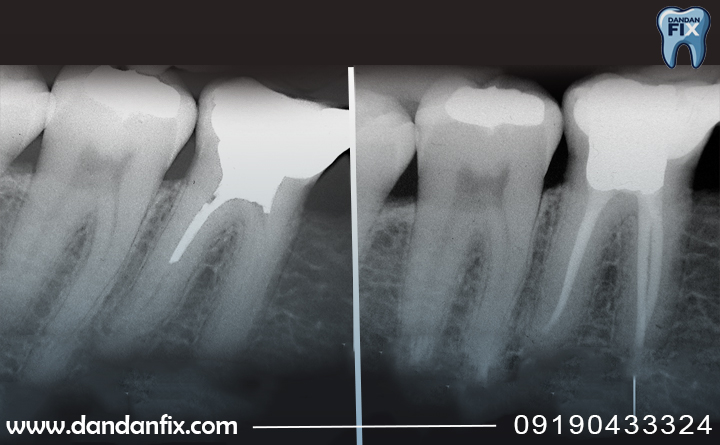

در ابتدا دندانپزشک دندان را معاینه میکند و با عکس رادیوگرافی، میزان پوسیدگی، محل عفونت و تعداد کانالهای ریشه را بررسی میکند. این مرحله برای برنامه ریزی دقیق درمان ضروری است. - مرحله دوم: بیحسی موضعی دندان

- وجود آبسه یا عفونت در عکس رادیوگرافی.